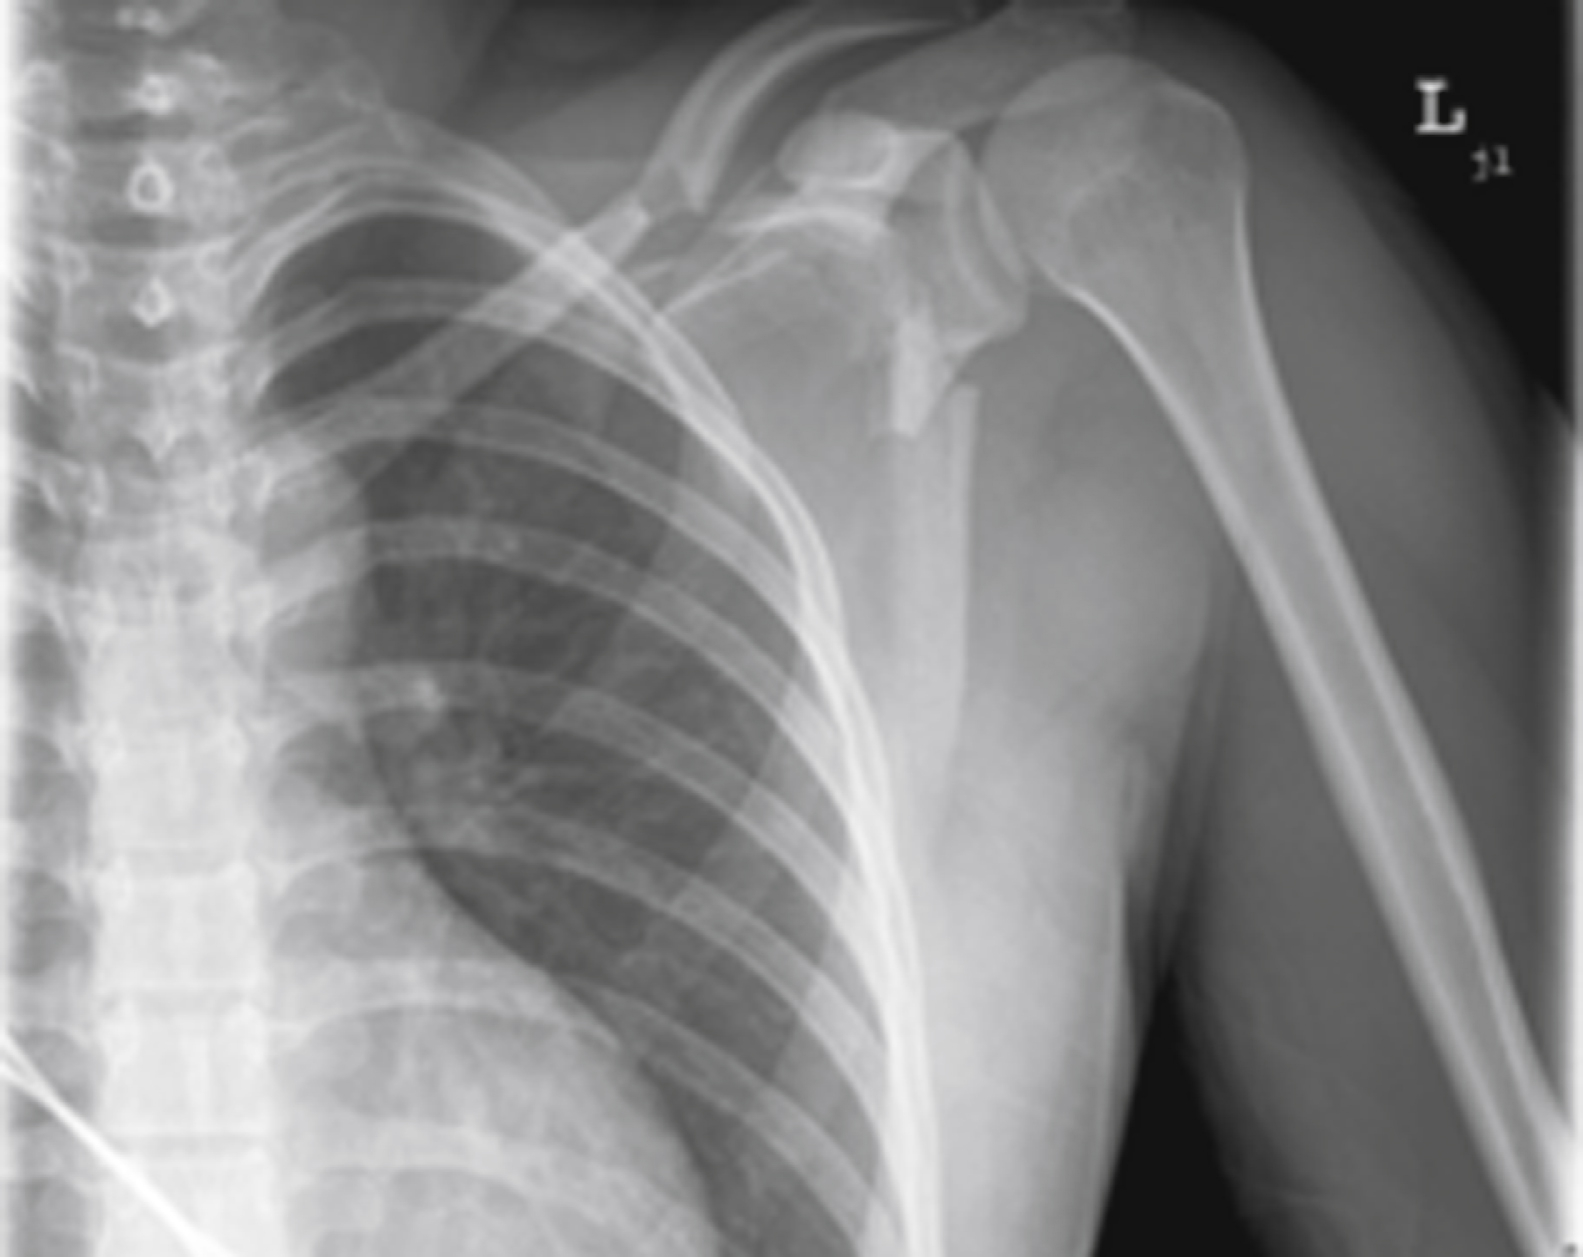

Although diagnosed clinically, sternoclavicular dislocation requires radiological confirmation. Findings on standard anteroposterior, oblique, and specialized (40-degree cephalic tilt) SCJ views are challenging to interpret. These dislocations and associated injuries are best visualized by a chest CT angiogram ( Fig. 45.16 ). POCUS can be a useful bedside adjunctive test.

This computed tomography (CT) scan shows posterior dislocation of the right sternoclavicular joint (SCJ; arrow ) with compression of the superior mediastinum.

Courtesy Donald Sauser, MD.